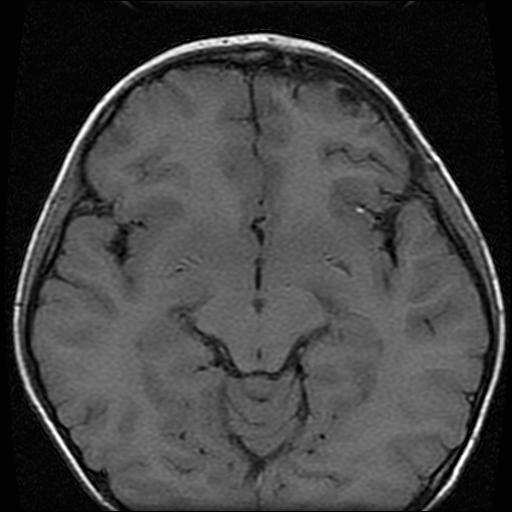

6岁小儿,左侧视神经瘤术后。现左侧视力减退。